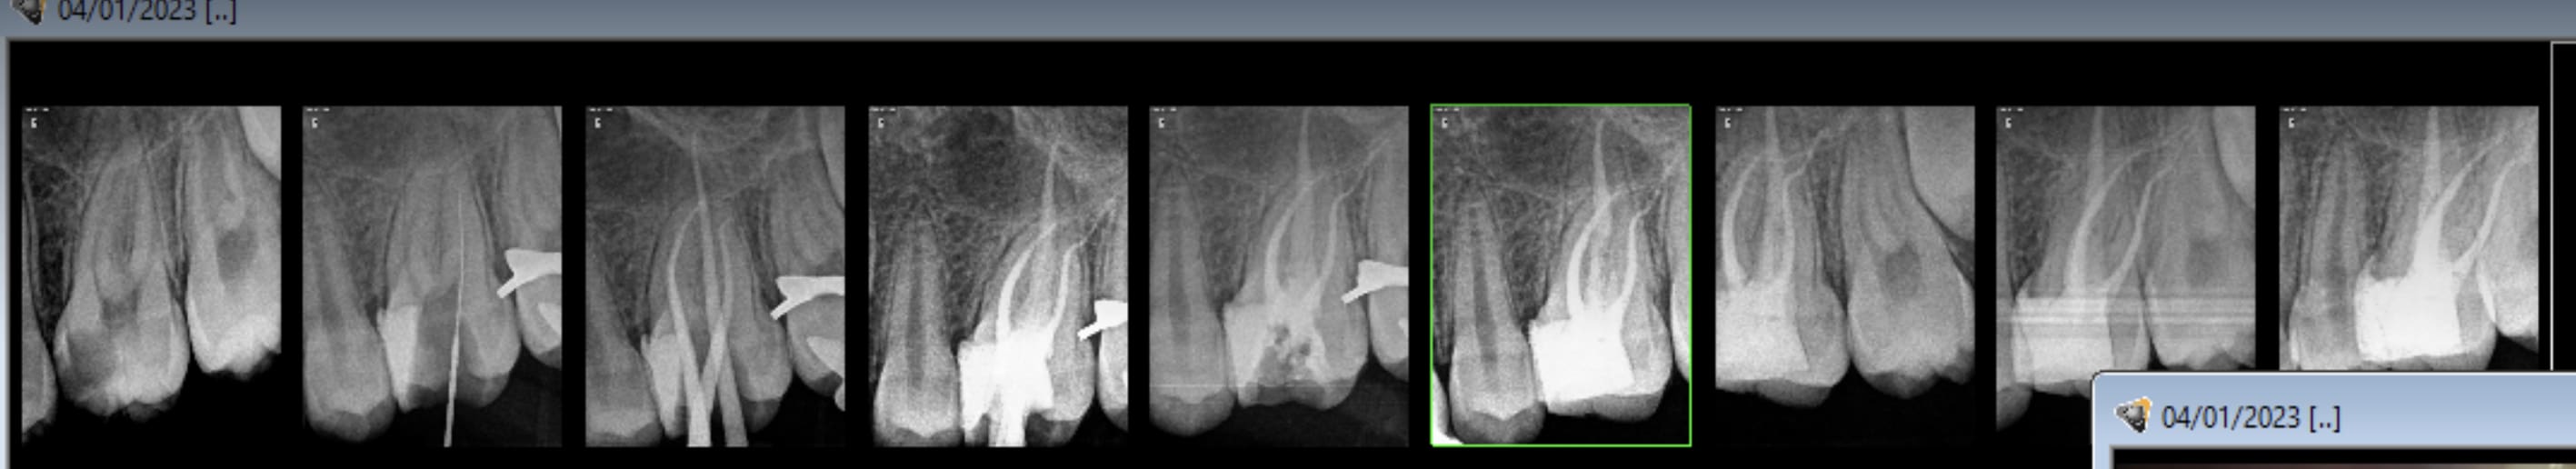

Je ne fais plus de radio MC en place depuis 5 ans

Uniquement localisateur d'apex + digue (pour que le localisateur ne merde pas) + radio pre op et radio post op

Le localisateur est infiniment plus precis qu'une radio MC qui n'est au final qu'une image 2D et n'indique qu'a +- 2mm ton apex

Perso neuf fois sur dix et pour des bios, je fais mesure sur la radio numérique, à ma grande surprise c'est vraiment précis, ça me permet de savoir si le localisateur est en défaut et mesure avec le localisateur.